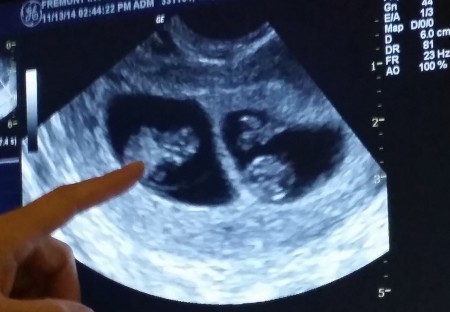

La fecundación in vitro fue un éxito, y la mujer gestante se quedó embarazada de gemelos en el primer intento.

"¡Fue uno de los momentos más felices de nuestra vida y de alguna manera empezamos a acariciar nuestro gran deseo, nuestro gran sueño que además venía por partida doble".

dos-sacos-gestacionales La Fecundación In Vitro había dado fruto. Maite y Oriol serían padres de gemelos